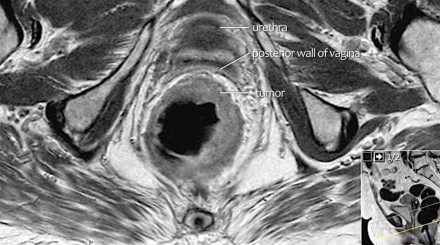

- T4: được chia T4a: khối u trực tiếp xâm lấn thanh mạc hoặc cân mạc treo trực tràng. T4b: khối u xâm lấn trực tiếp hoặc dính vào các tạng, cơ quan khác.

Hình 6. Sự giảm tín hiệu của khối u xâm lấn vào thành sau âm đạo